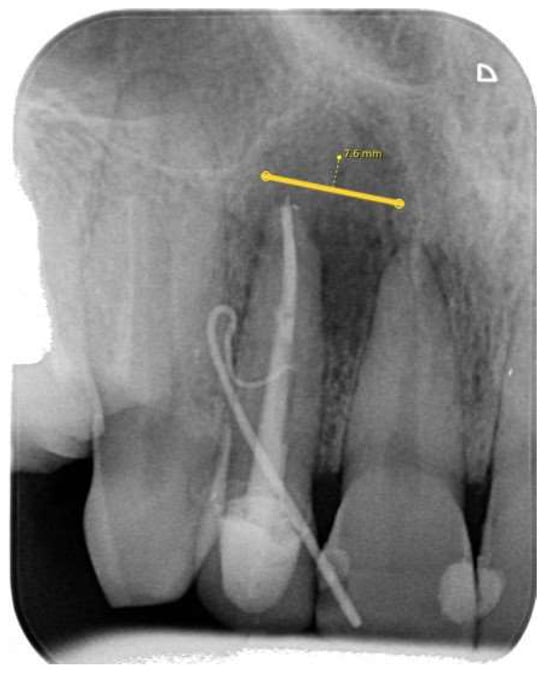

2.3.1. Periapical (PA) Radiography Examination and Evaluation

- Category 1: no discernible periapical lesion was identified;

- Category 2: a periapical lesion was possibly present, however, the distinction was not unequivocal;

- Category 3: a periapical lesion was definitively observed.